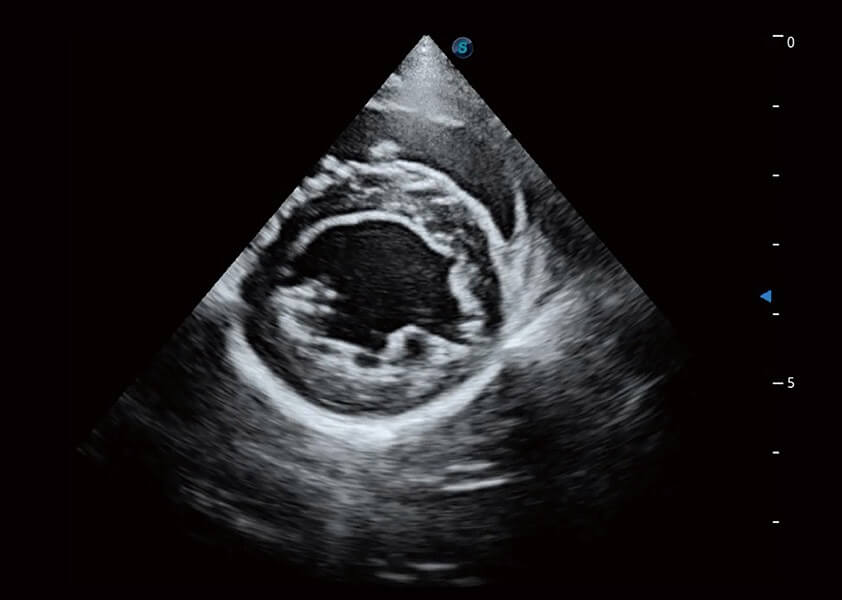

ProPet 60 作为一款高端台式动物超声设备,为动物医生的日常诊断提供了一系列贴合动物临床需求、解决临床实际问题的高级成像功能。凭借全系列高清探头,满足医生对腹部、心脏、生殖、浅表、肌骨等成像的所有需求,切实帮助您提升检查效率,提高诊断信心。

动物是人类最亲密的朋友和最值得信赖的伙伴。云顶集团官网也一直致力于探索动物专用的超声影像解决方案。 全新推出的ProPet系列,是云顶集团官网在动物超声影像智能化、专业化、精准化的一次跨越式革新。动物不能用言语来表述自己的不适,通过超声影像,ProPet系列搭建了动物医生与不同物种沟通的“桥梁”,为动物医生注入了“治愈之力”。